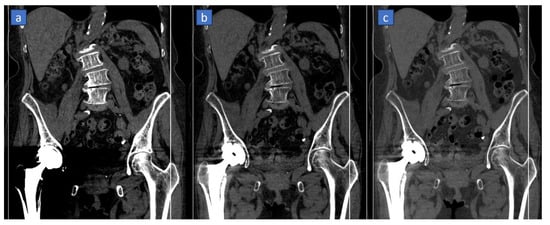

4.3. Reduce Metal Artifacts